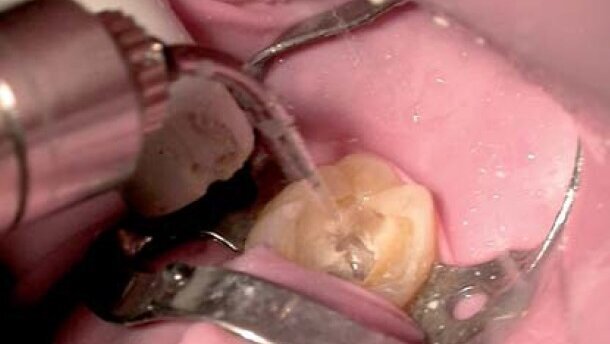

Preparacja ubytku i usuwanie próchnicy

Pomysł, że laser (mniej traumatyczny dla pacjenta) mógł zastąpić wiertło doprowadził do wprowadzenia tego instrumentu do stomatologii dziecięcej. Laser w przeciwieństwie do tradycyjnego wiertła opracowuje tkankę twardą bez kontaktu z powierzchnią zęba. Nie wytwarza także wibracji, nie wydaje dźwięku wiercenia, a jego zastosowanie jest mniej bolesne. Wiele badań i raportów klinicznych wykazało, że laser wprowadza element bezpieczeństwa do zabiegu, gdy jest stosowany jako alternatywa dla narzędzi obrotowych w stomatologii rekonstrukcyjnej, nawet w przypadku leczenia bardzo małych dzieci. Technika laserowa otwiera zatem drogę do minimalnej interwencji, która skupia się wyłącznie na tkance próchniczej.

Przeprowadzono badania nad zastosowaniem rozmaitych laserów. Laser CO2 wywoływał szkody termiczne leczonej tkanki. Inne eksperymenty kliniczne wykazały możliwość leczenia próchnicy szkliwa u dzieci laserem Nd:YAG. Niestety, analiza mikromorfologiczna zębów mlecznych poddanych zabiegowi laserowemu wykazała uszkodzenie tkanek zęba. Obecnie do leczenia tkanek twardych wykorzystuje się 2 typy laserów: Er, Cr: YSGG (2.780 nm) oraz Er: YAG (2.940 nm). Najwcześniejsze badania dotyczące stosowania laserów erbowych do preparacji ubytków i usuwania próchnicy powstały w 1989 r., kiedy Hibst i Keller ocenili wydajność lasera Er:YAG w nacinaniu tkanki twardej. Przez pierwsze 10 lat różni autorzy zajmowali się wieloma parametrami i zmiennymi laserów erbowych, wykorzystywanych do preparacji ubytków i usuwania próchnicy. Badano efekty morfologiczne wpływu na tkankę twardą i miazgę, a także wpływ gęstości energii, wskaźnika powtórzeń impulsów oraz chłodzenia sprayem wodnym.

W 1998 r. Moritz i inny odkryli, że rezultaty wytrawiania szkliwa laserem były takie same jak otrzymane poprzez wytrawianie kwasem ortofosforowym. Olivi i inni potwierdzili skuteczność lasera erbowego w preparacji ubytku i usuwaniu tkanki próchniczej.